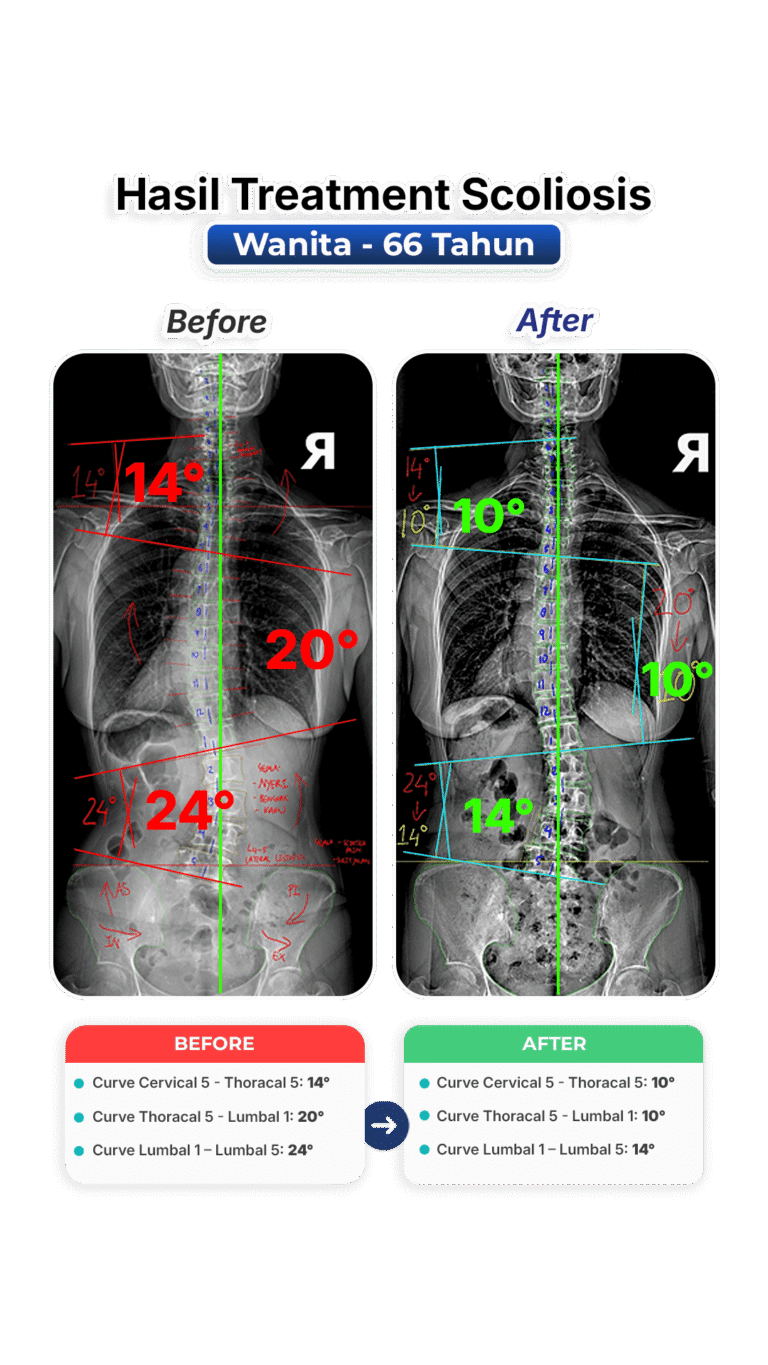

Perubahan nyata setelah mengikuti program terapi skoliosis di VLife Medical Galaxy Mall 3.

Perawatan scoliosis dilakukan melalui evaluasi tulang belakang menyeluruh, program terapi bertahap, fokus keseimbangan postur, mengurangi nyeri, memperlambat progres kelengkungan, serta meningkatkan fungsi gerak harian pasien secara aman dan terkontrol medis.

Penanganan skoliosis berbasis evaluasi postur menyeluruh, terapi manual khusus, latihan koreksi, serta pemantauan progres di setiap sesi. Dibuat untuk remaja dan dewasa yang ingin mengendalikan kelengkungan skoliosis dan mengurangi nyeri.